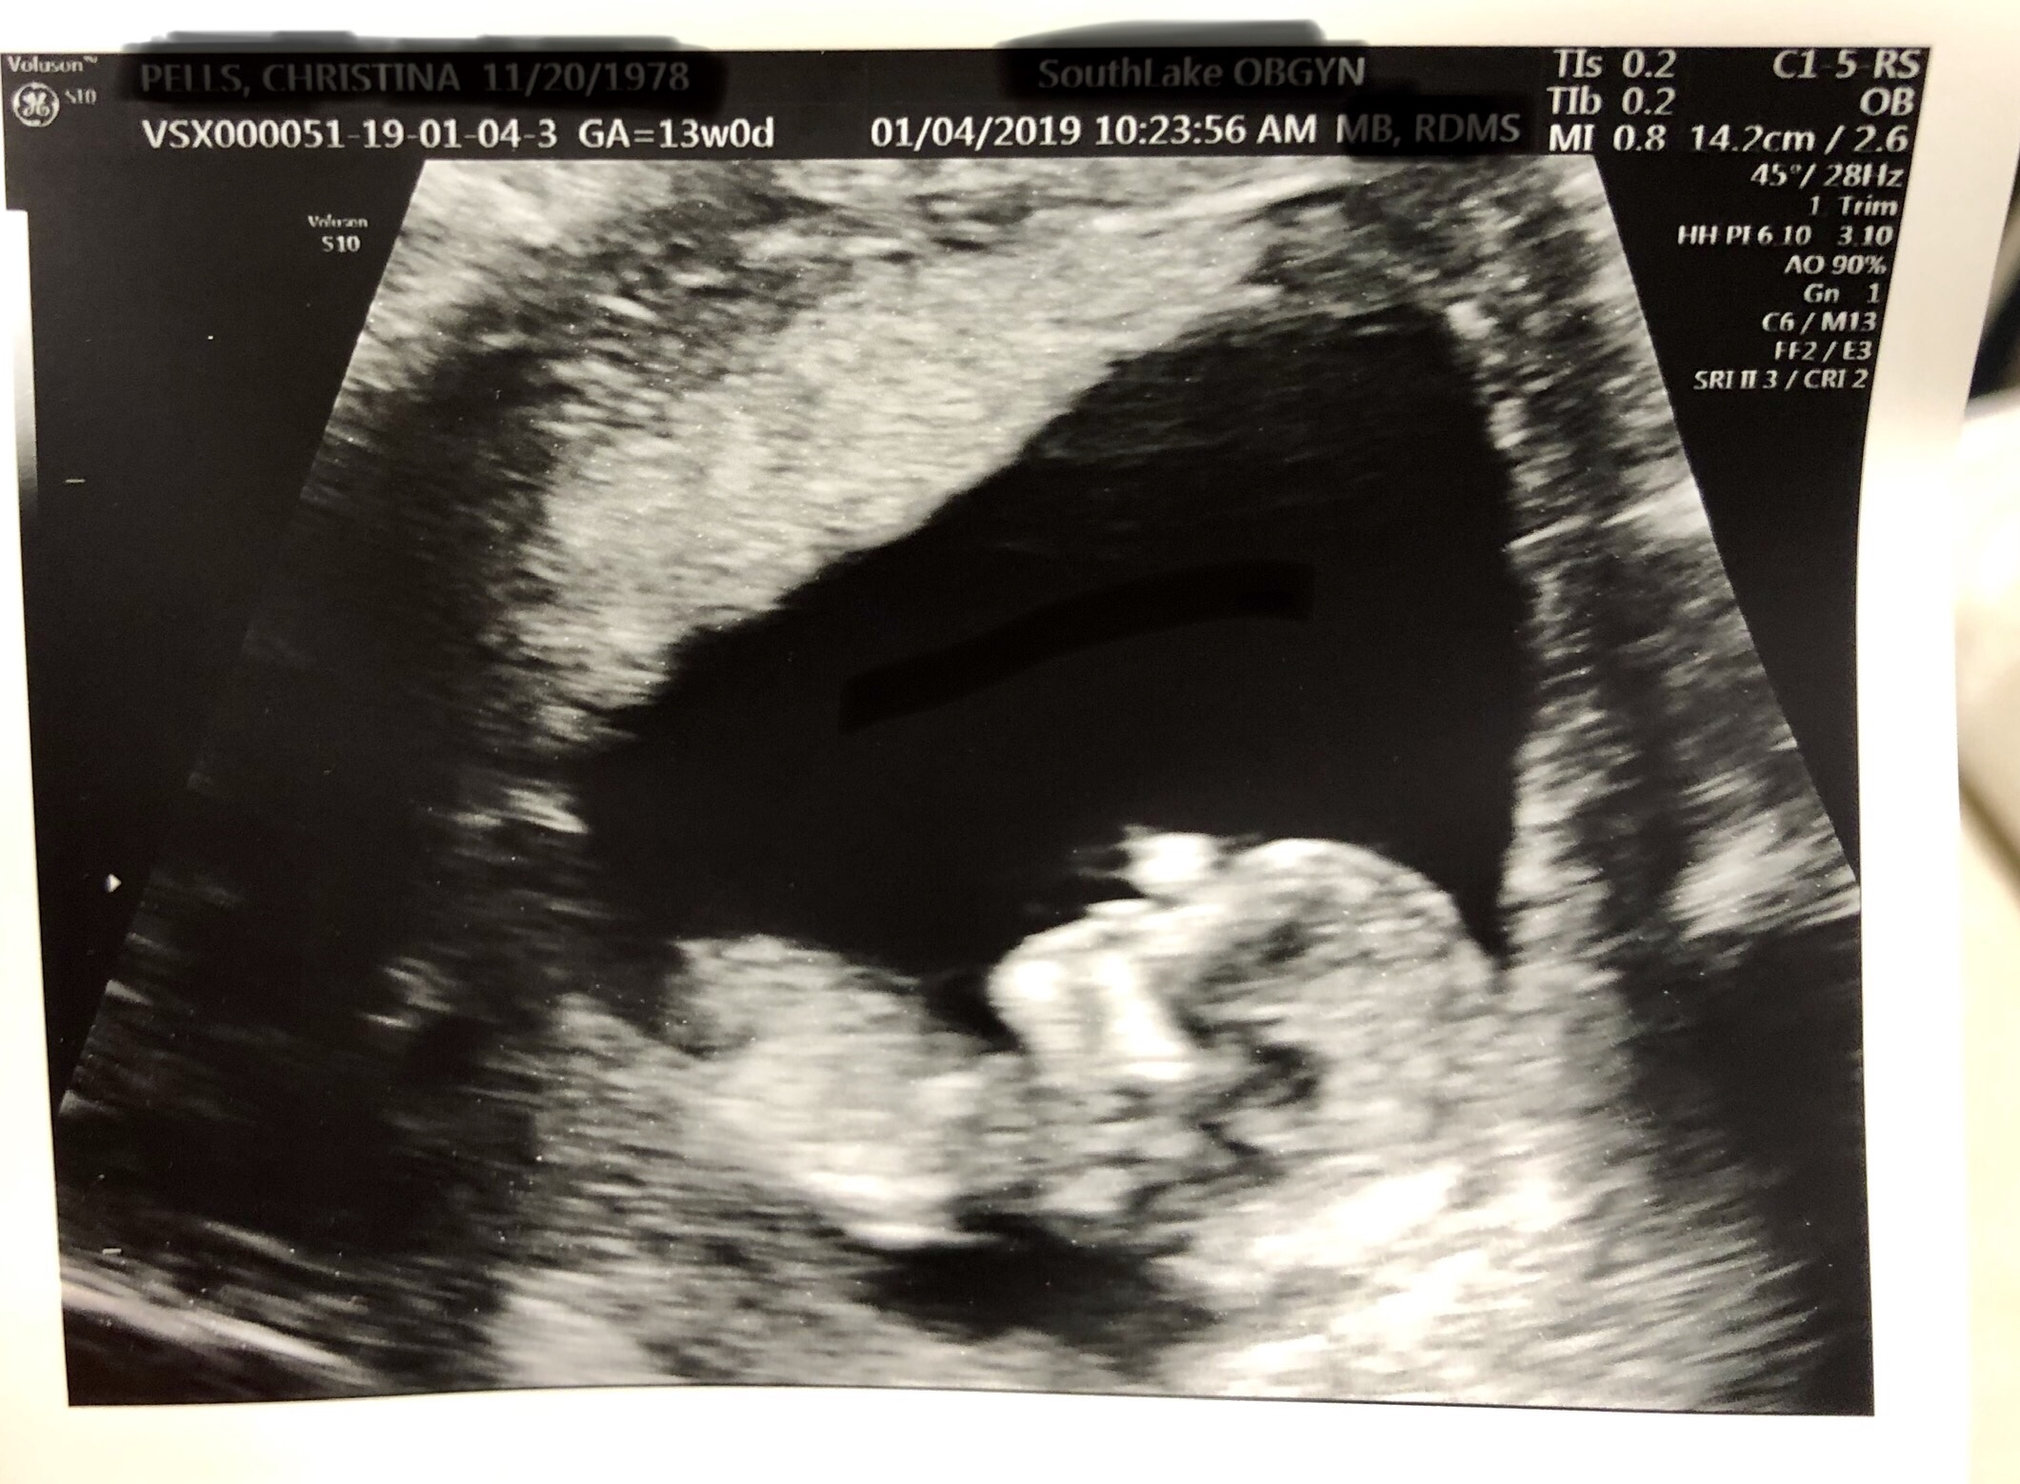

This pic was on Thursday at 13weeks2days. Can’t believe we are almost in our second trimester! She was moving around and bobbing her head. Love seeing her so active